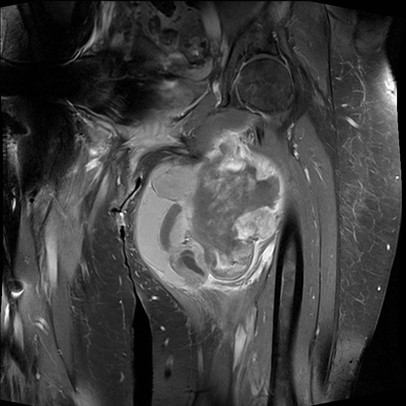

MRI

Anatomy / neurovascular involvement

Sarcoma buttock